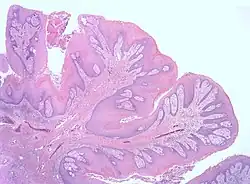

| Micrograph showing a squamous papilloma of the tongue. H&E stain. | |

It appears as an exophytic mass with a cauliflower-like appearance. The lesion may be white, red, or normal in color. It appears as a sessile or pedunculated mass. Histopathology typically shows papillomatosis protrusions and/or dysplasia.[9]

Histopathology of the same papilloma.

Histopathology of the same papilloma.